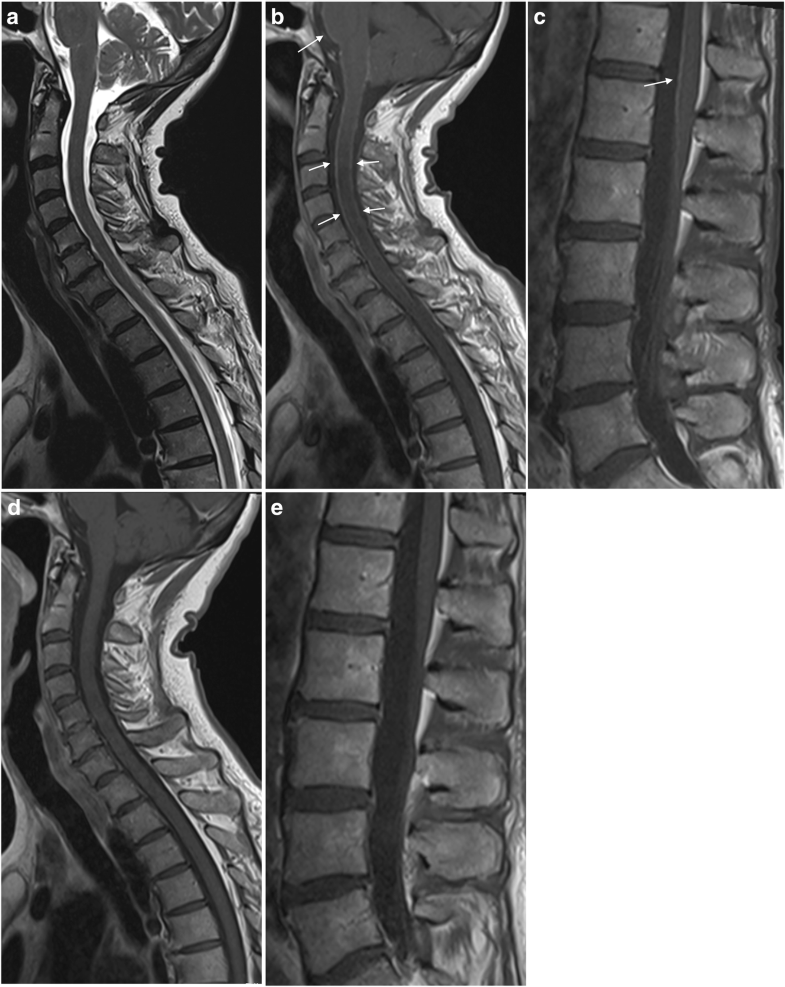

21+ Lyme Disease Radiology Brain Pictures. Unfortunately, my story is all too common. Lyme disease, also known as lyme borreliosis, is an infectious disease caused by the borrelia bacterium which is spread by ticks.

I need to let everyone know how much hope is really out there, and that you can get your life back. In the united states, this is usually a bacterium called borrelia burgdorferi. The neurological symptoms of lyme disease are some of the most confused with other illnesses. Lyme disease is an infection resulting from the bacteria, borrelia burgdorferi, which enter the body when certain infected ticks bite.